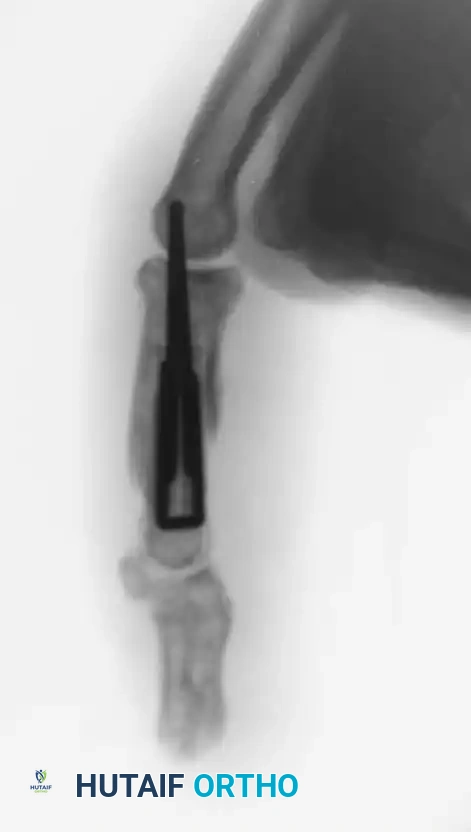

Percutaneous Techniques: Belsky-Eaton Pinning

Sometimes an unstable oblique fracture of a middle or proximal phalanx can be treated by closed reduction and percutaneous pinning. Belsky and Eaton described a highly effective technique for pinning multiple proximal phalangeal fractures without opening the fracture site.

Step-by-Step Technique:

* The fractured phalanx is held reduced with the MCP joint flexed to 90 degrees. This tightens the collateral ligaments, using them as a tension band to align the proximal fragment.

* A single K-wire is drilled from the dorsal aspect of the metacarpal head, passing across the MCP joint and straight down the medullary canal of the proximal phalanx to cross the fracture.

* Crucial Step: The wire must not cross the PIP joint.

* Leave the wire exposed proximally (bent outside the skin) to allow for easy removal in the clinic at 3 to 4 weeks.